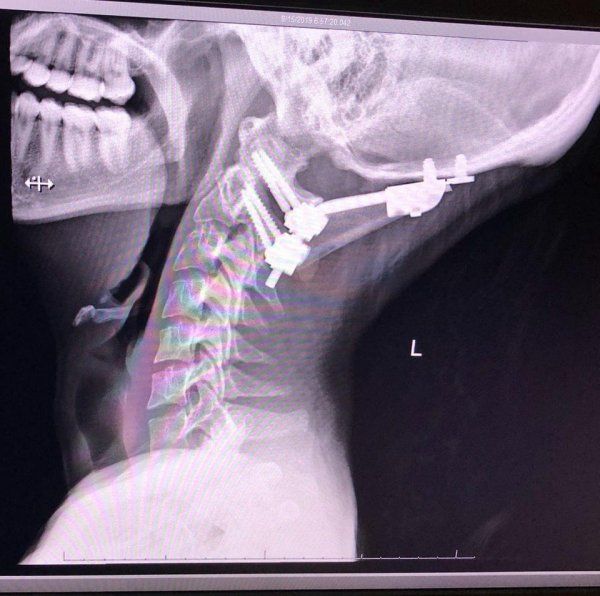

Медицинское приспособление для лечения перелома шеи